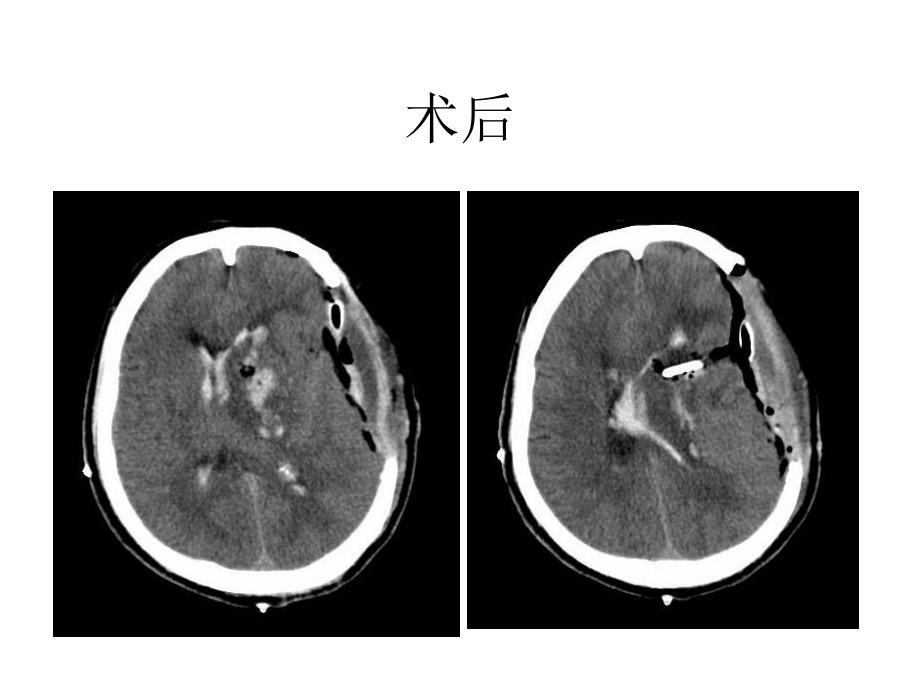

1、脑外科教学查房术前术后 汇报病史 临床体检 辅助检查 病史小结 诊断及依据 鉴别诊断 治疗方案 基底节?基底节区脑出血 基底节|尾状核 豆状核|壳核 苍白球|新纹状体 旧纹状体|病变时出现肌张力降低,运动过多 病变时出现肌张力增高,运动减少 基底节区,影像学名词?包括,基底节及内囊,为一不太明确的区域。内囊,概念很明确,包括内囊前肢、内囊膝部及内囊后肢。基底节,或基底核,指大脑的中心灰质核团,包括尾状核、豆状核、杏仁核和屏状核。广义的基底节是将红核、黑质、及丘脑底核也作为基底神经节的一部分。病理 微动脉瘤 小动脉壁的脂质透明变性病因 原发性脑损害 继发性脑损害 颅内压升高鉴别诊断 出血性脑梗死

2、 动脉瘤破裂 脑动静脉畸形 海绵状血管瘤 烟雾病 颅内肿瘤出血 血液系统疾病内科治疗 一般处理 脑出血急性期高血压的处理 降低颅内压 激素的应用 止血剂的应用脑出血急性期高血压的处理a 脑血流量自动调节机能:人体在不同状态下血压经常变动,但脑血流量则保持不变。脑灌注压:CPP=MAP-ICP脑血流量自动调节对血压的容许变动范围是:MAP=70120mmHg脑出血急性期高血压的处理b 血压的容许的范围内变动时,脑血流量保持不变;MAP低于70mmHg时,脑血流量将明显减少,导致低氧缺血损害,继发急性脑水肿和颅内压升高;若MAP高于120 mmHg,小动脉收缩将被突破而变为被动性扩张,导致过度灌注

3、加重颅高压。而在慢性高血压患者,因其对较高的血压已渐适应,其脑血流的血压调节上限将会上移,甚至高达250mmHg。降低颅内压 甘露醇的药理 使用方法 注意事项 误区外科治疗 级:患者已处于晚期,手术很难奏效。级最适合手术。、级绝大多数适合手术治疗,依病情而定,如血肿量大、内科治疗不佳等。级多发于皮质下或壳核,一般不需手术,但血肿量30ml可考虑手术。手术方法 开颅血肿清除术 钻孔微创颅内血肿清除术 手术录像 脑卒中的外科治疗.rmvb影响手术效果的因素 患者年纪 意识水平:出血量及部位:手术时机:手术方式:常见并发症的预防和治疗 消化道出血 肺部感染 急性肺水肿恢复期治疗 急性期康复治疗 恢复期的治疗1.功能锻炼2.药物治疗3.高压氧治疗4.语言训练5.心理康复谢谢